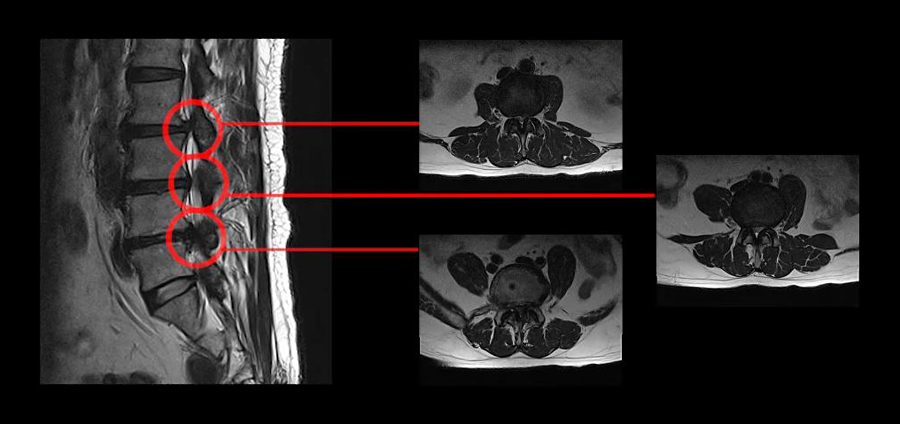

모커리 협착증 근육재활치료를 받은 환자의 MRI

위 MRI는 강남 모커리한방병원에서 협착증 재활치료를 받으신 환자의 MRI입니다. 보시다시피 세 마디의 척추관이 심하게 막혀있으며 허리도 못 펴고 움직이지도, 걷지도 못하는 상태였습니다. 협착이 너무 극심하다 보니 대학병원에서는 수술이 어렵다고 참고 살라고 할 정도였고, 다른 유명 척추병원에서는 3주에 걸쳐 세 번의 수술을 해야 한다는 말을 들으셨습니다.

이분이 만약 척추협착증원인 중 좁아진 척추관으로 인한 신경 눌림 때문에, 오로지 그 이유만으로 증상이 나온 것이었다면 어떠한 비수술적 치료를 받아도 증상이 좋아지지 않아야 정상이겠죠. 그런데 만약 이분이 협착증 재활치료로 증상이 90% 이상 사라졌다면, 이게 어떻게 설명이 가능할까요? 아래 영상을 클릭하셔서 이 환자분의 치료후기를 꼭 들어보시길 바랍니다.